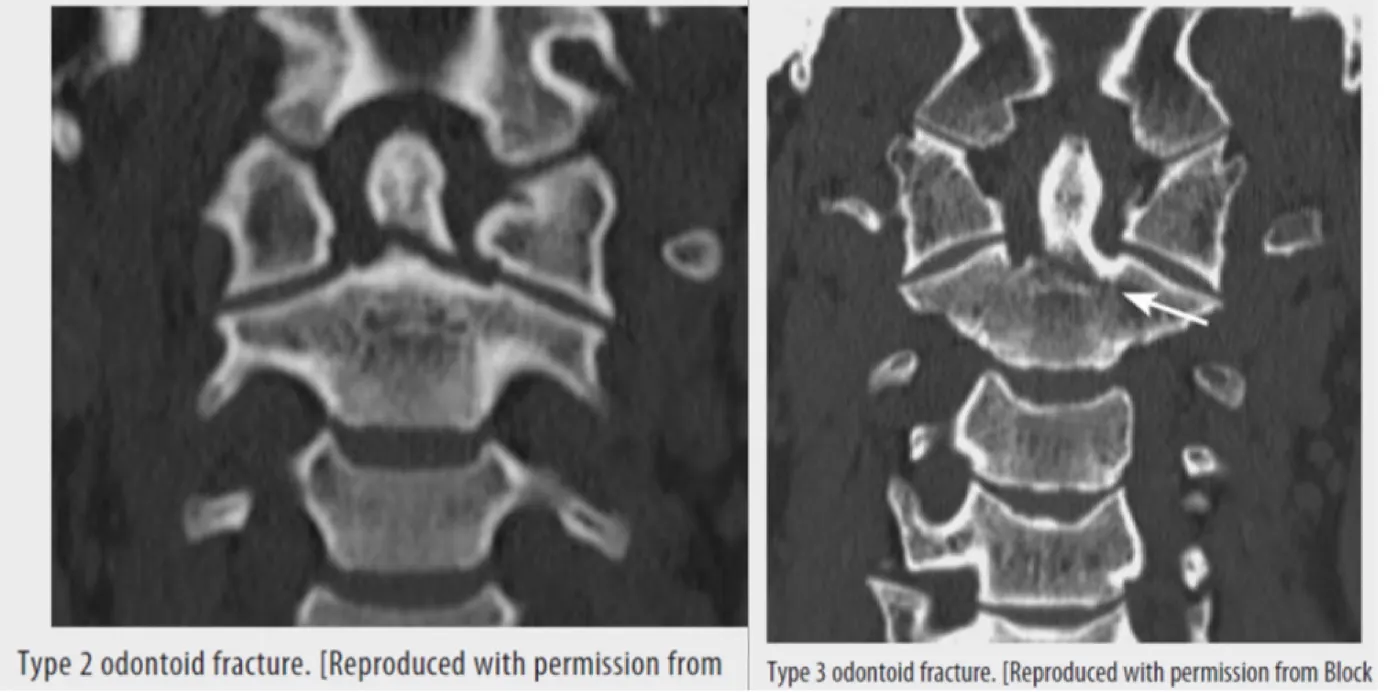

③ Odontoid (dens) fracture (type Ⅱ & Ⅲ are unstable)

① Odontoid Fx

: Type Ⅰ (Avulsion of the tip : stable), Type Ⅱ (Junction of odontoid : unstable),

Type Ⅲ (Superior portion of C2 : unstable)